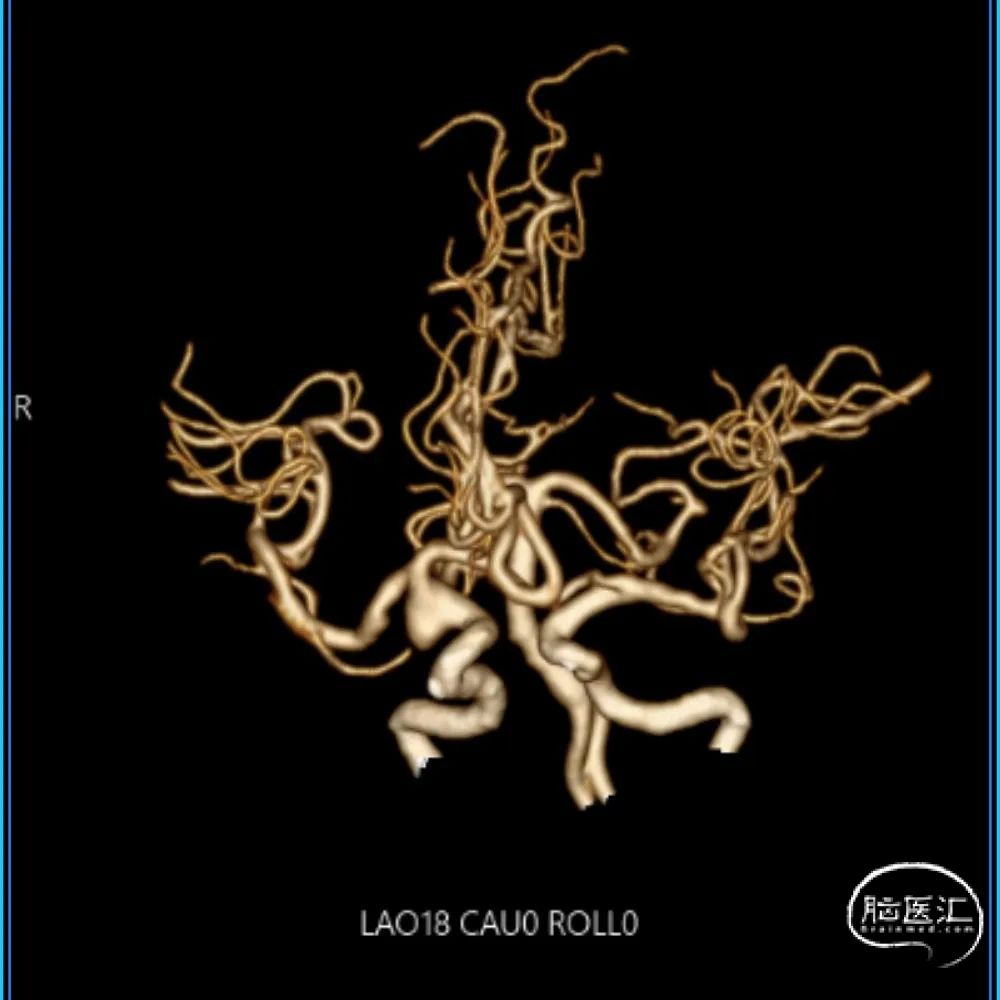

CTA:右侧颈内动脉C7段动脉瘤。

老年女性患者,检查发现右侧颈内动脉C7段大动脉瘤,动脉瘤直径大于10mm,形态不规则,宽颈,手术指征明确,既往高血压、肿瘤病史,首选微创介入手术,术中造影证实动脉瘤直径大于10mm,绝对宽颈,形态不规则,局部仔瘤改变,右侧脉络膜前动脉从瘤体发出;微创介入血流导向装置是较优选择。

DSA造影:

工作角度:

大动脉瘤的微创介入栓塞治疗存在需要支架辅助,瘤颈处理困难、复发率高、费用高等难点;血流导向密网支架置入是较优选择,操作相对简单,不用填塞弹簧圈,完整覆盖瘤颈,远期明显降低再复发概率。本病例为右侧颈内动脉C7段累及脉络膜前动脉的大动脉瘤,该部位解剖结构复杂,周围血管分支多,在操作过程中要避免损伤正常血管,否则会引发严重脑缺血事件;其次,动脉瘤与脉络膜前动脉关系密切,既要处理好动脉瘤,又要保证脉络膜前动脉的血供不受影响,这对手术操作精度要求较高;再者,瘤颈的处理较为棘手,瘤颈较宽,传统弹簧圈栓塞难以达到理想效果,且容易复发。血流导向密网支架置入可解决这些问题,术前需借助3D-DSA,全面评估动脉瘤大小、形态、瘤颈宽度、与周围血管关系,制定精准手术方案。操作时,微导管的到位是关键一步,要在路径图引导下,小心、轻柔操作,避免刺激血管引发痉挛或动脉瘤破裂。释放支架过程中,要注意关注支架位置和贴壁情况。释放后要通过多角度造影,确认支架完全覆盖瘤颈,且支架内血流通畅,分支血管未受影响。同时,术后要密切观察患者神经功能变化,预防血栓形成、血管痉挛等并发症,及时给予抗血小板、解痉等药物治疗。